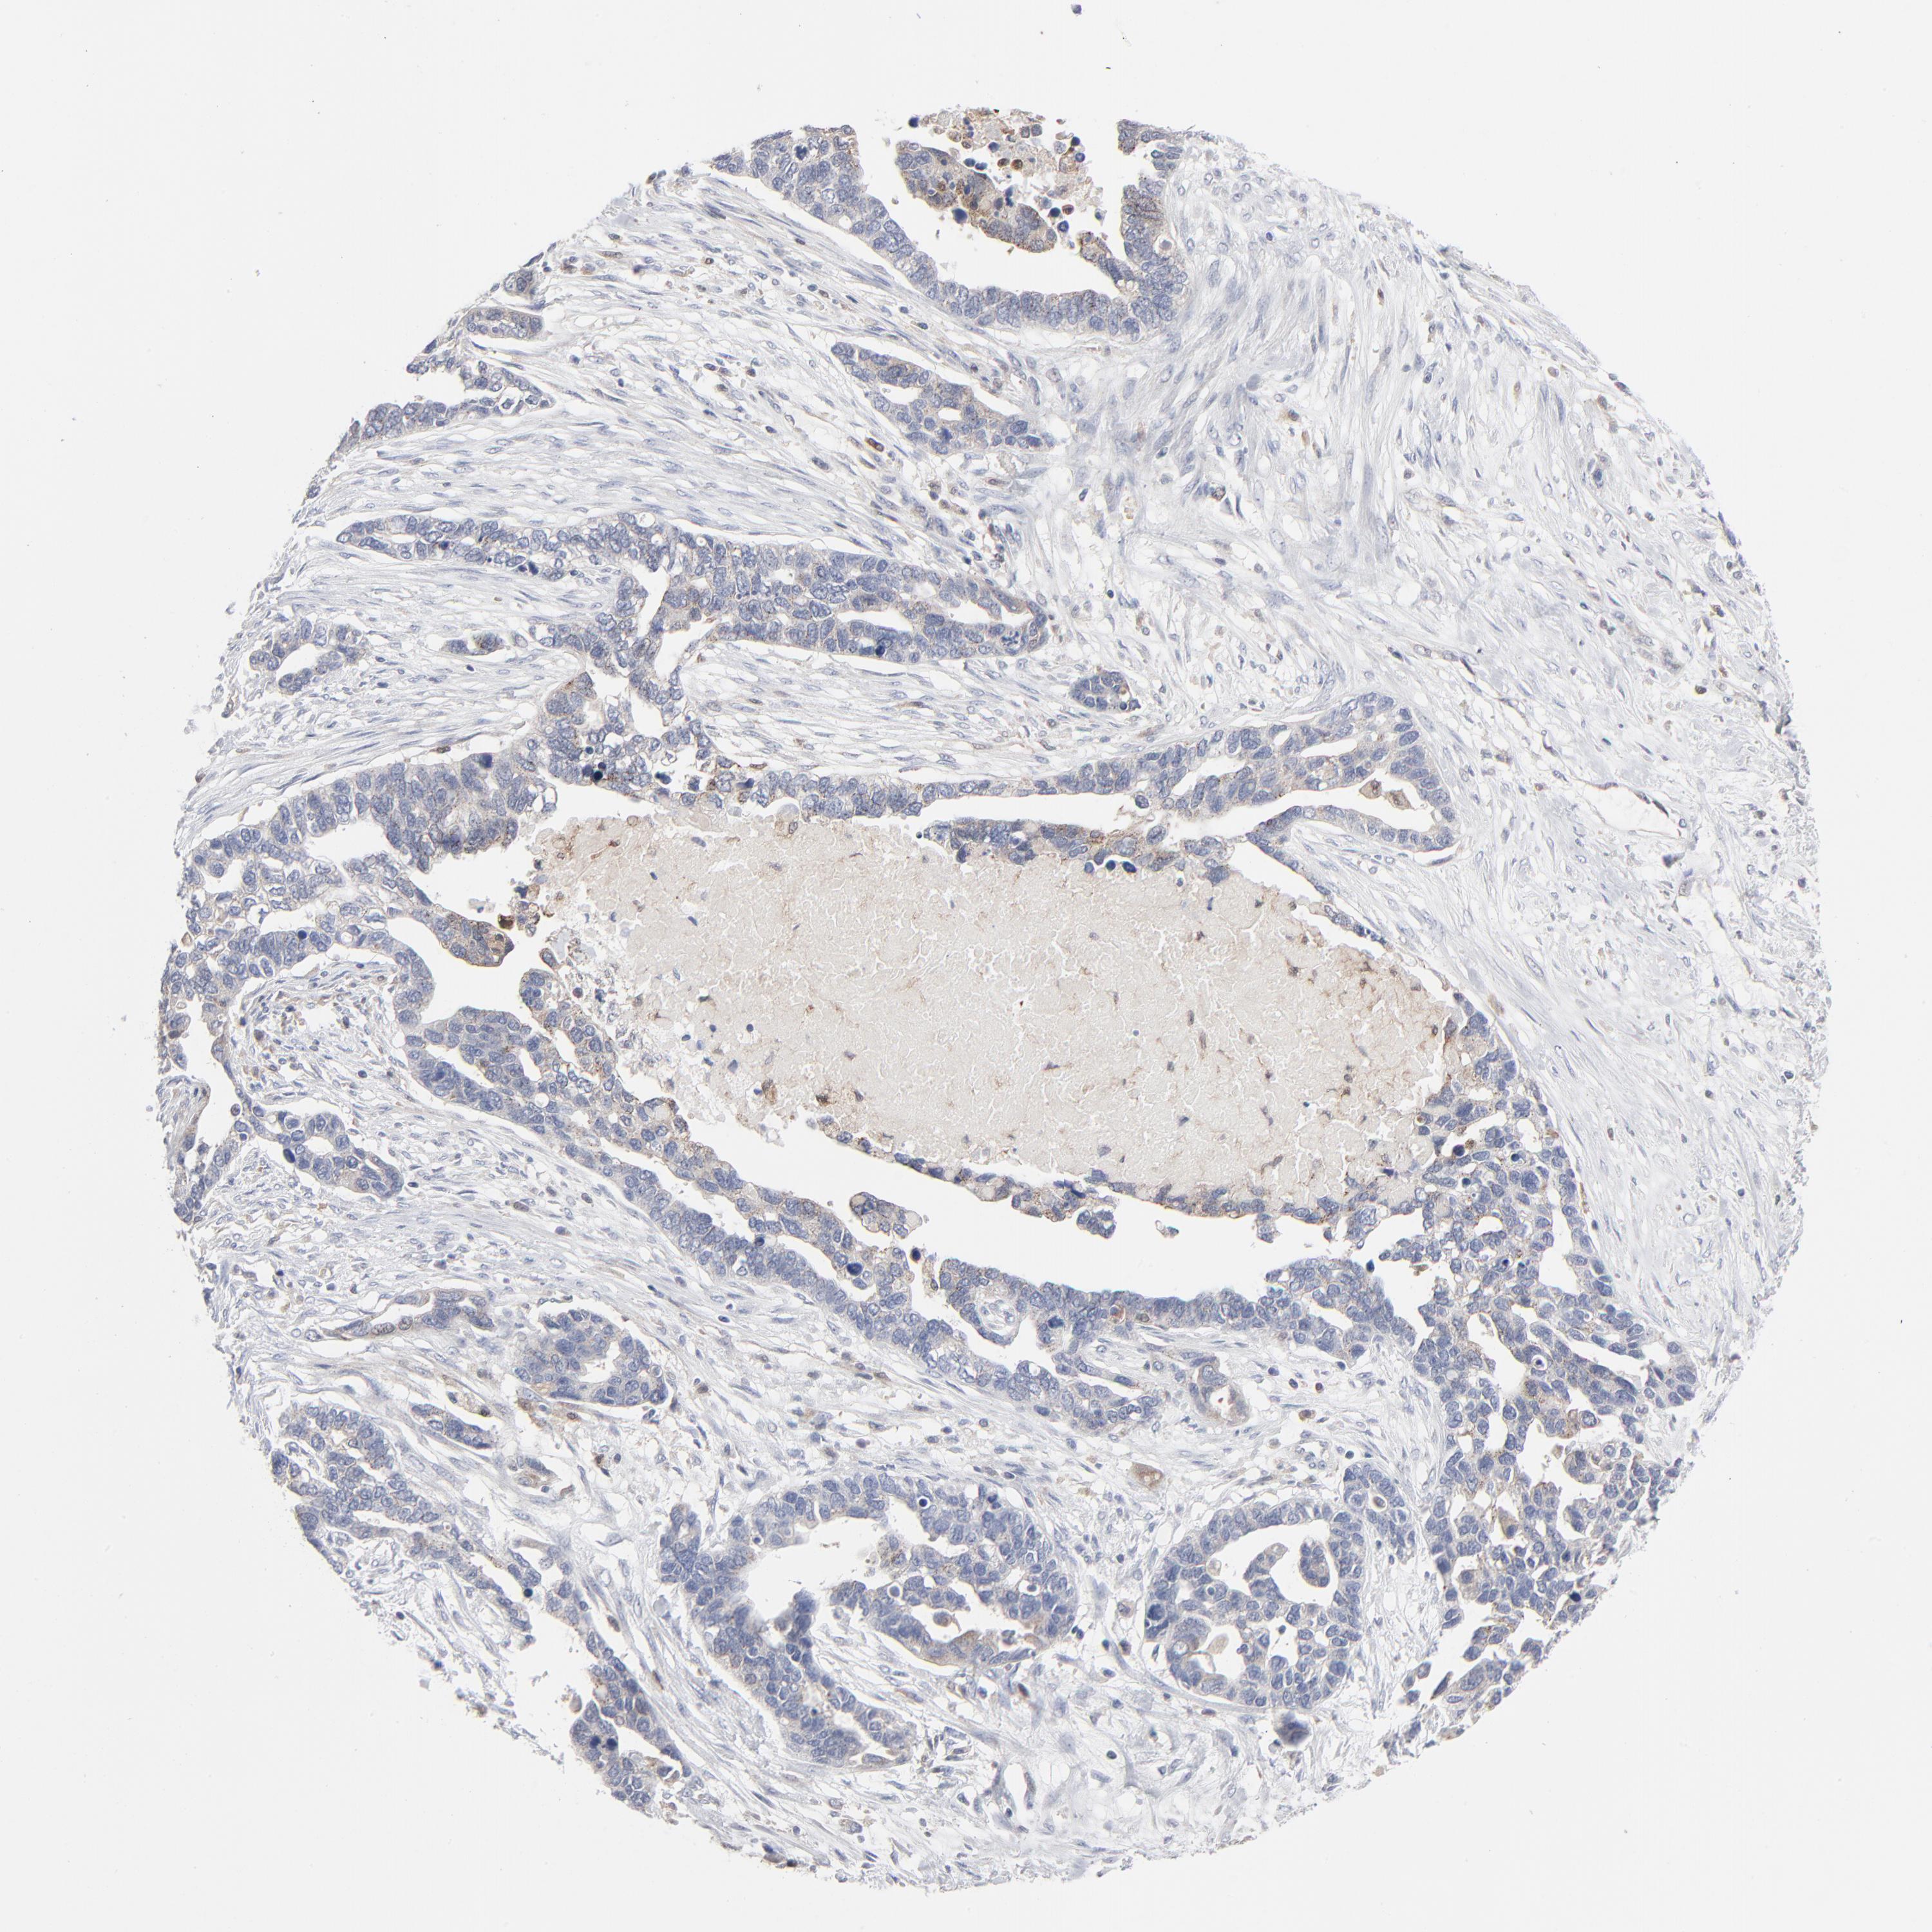

OVARIAN CANCER - Protein expressioni

A mouse-over function shows sample information and annotation data. Click on an image to view it in a full screen mode. Samples can be filtered based on level of antibody staining by selecting one or several of the following categories: high, medium, low and not detected. The assay and annotation is described here.

Note that samples used for immunohistochemistry by the Human Protein Atlas do not correspond to samples in the TCGA dataset.

Antibody stainingi

Antibody staining in the annotated cell types in the current human tissue is reported as not detected, low, medium, or high, based on conventional immunohistochemistry profiling in selected tissues. This score is based on the combination of the staining intensity and fraction of stained cells.

Each image is clickable and will lead to virtual microscopy that enables deeper exploration of all samples and also displays staining intensity scores, fraction scores and subcellular localization as well as patient and tissue information for each sample.

Antibody HPA000722

Antibody CAB003771

Staining

High

Medium

Low

Not detected

Intensity

Strong

Moderate

Weak

Negative

Quantity

>75%

75%-25%

<25%

None

Location

Nuclear

Cytoplasmic/membranous

Cytoplasmic/membranous,nuclear

Cystadenocarcinoma, mucinous, NOS

Carcinoma, endometroid

Cystadenocarcinoma, serous, NOS